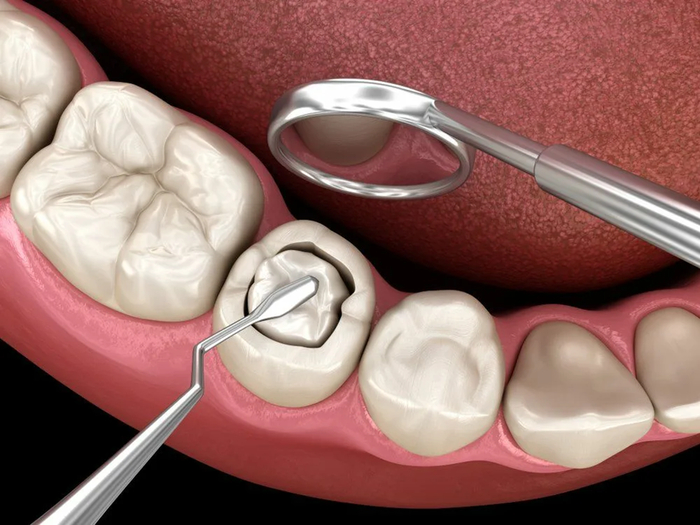

2) Лечение кариеса с применением пломбировочных материалов отечественного производства — при разрушении зуба менее чем на 50 %.

Важный нюанс: если разрушение превышает половину жевательной поверхности зуба, формально пломбу ставить не положено — должны направить к ортопеду (протезисту) на коронку. На практике врачи часто идут на уступки и восстанавливают зуб целиком пломбой, чтобы избежать недовольства пациентов.

О качестве: за 15-20 минут приёма можно лишь осмотреть пациента и сделать анестезию. То, что пломба «не выпадает», — не критерий качества. Главная задача пломбы — обеспечить герметичное краевое прилегание, чтобы предотвратить повторный кариес. Качественная работа занимает от 40 минут до 2 часов.